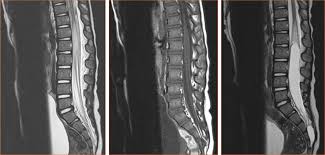

El problema fue identificado como una mielitis transversa, un trastorno neurológico que causa inflamación de la médula espinal, explicó Francis Collins, director de los Institutos Nacionales de Salud de Estados Unidos.

-Se trata de un trastorno neurológico causado por inflamación en ambos lados de un nivel, o segmento, de la médula espinal.

-Los episodios de inflamación puede dañar o destruir la mielina, que es una sustancia grasa aislante que cubre las fibras celulares nerviosas.

-Esto puede provocar cicatrices en el sistema nervioso, provocando una interrupción en la comunicación entre los nervios de la médula espinal y el resto del cuerpo.